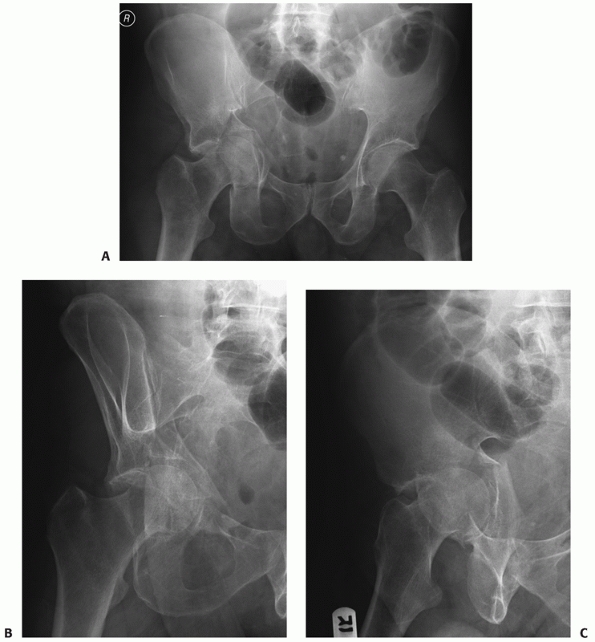

FIGURE 45-21 Radiographic appearance of the anterior column fracture. A.

The AP view demonstrates the fracture from the iliac crest to the hip joint with disruption of the roof. A small area of comminution at the pelvic brim is noted. The ischial ramus fracture is also noted. B. The obturator oblique demonstrates a single break in the iliopectineal line where the anterior column fracture crosses the pelvic brim. Although difficult to see, the disruption of the ilium can be appreciated as a reduplication of the cortical lines of the internal iliac and fossa and external wing of the ilium. C. The iliac oblique view confirms the posterior border of the bone to be intact. |

Anterior column fractures separate the anterior border of the

innominate bone from the intact ilium. The type of anterior column

fracture is named by the location where the fracture exits the anterior

aspect of the bone. High anterior column fractures exit the iliac

crest, intermediate fractures exit the anterior superior iliac spine,

low fractures exit the psoas gutter just below the anterior inferior

iliac spine, and very low anterior column fractures exit the bone at

the iliopectineal eminence (Fig. 45-20). All

anterior column fractures, regardless of where they exit the bone

superiorly, cross the pelvic brim, proceed down the quadrilateral

surface, and enter the ischiopubic notch, ultimately ending in a

fracture of the inferior ramus. Typically, the lower the fracture

crosses the anterior border of the bone, the more inferior is the site

of fracture of the ischiopubic ramus. As in the anterior wall

fractures, it is common for a portion of the quadrilateral surface to

be detached as a separate fragment but the posterior border of the

innominate bone remains intact. The iliopectineal line is disrupted in

one location on the obturator oblique and AP views. The very low

anterior column fracture can be distinguished from the typical anterior

wall fracture in that it has a fracture of the inferior pubic ramus and

a single break in the iliopectineal line. The femoral head displaces

with the anterior column fracture. The typical displacement

is an external rotation of the anterior fragment about the femoral head, allowing the head to move medial and superior (Fig. 45-21).